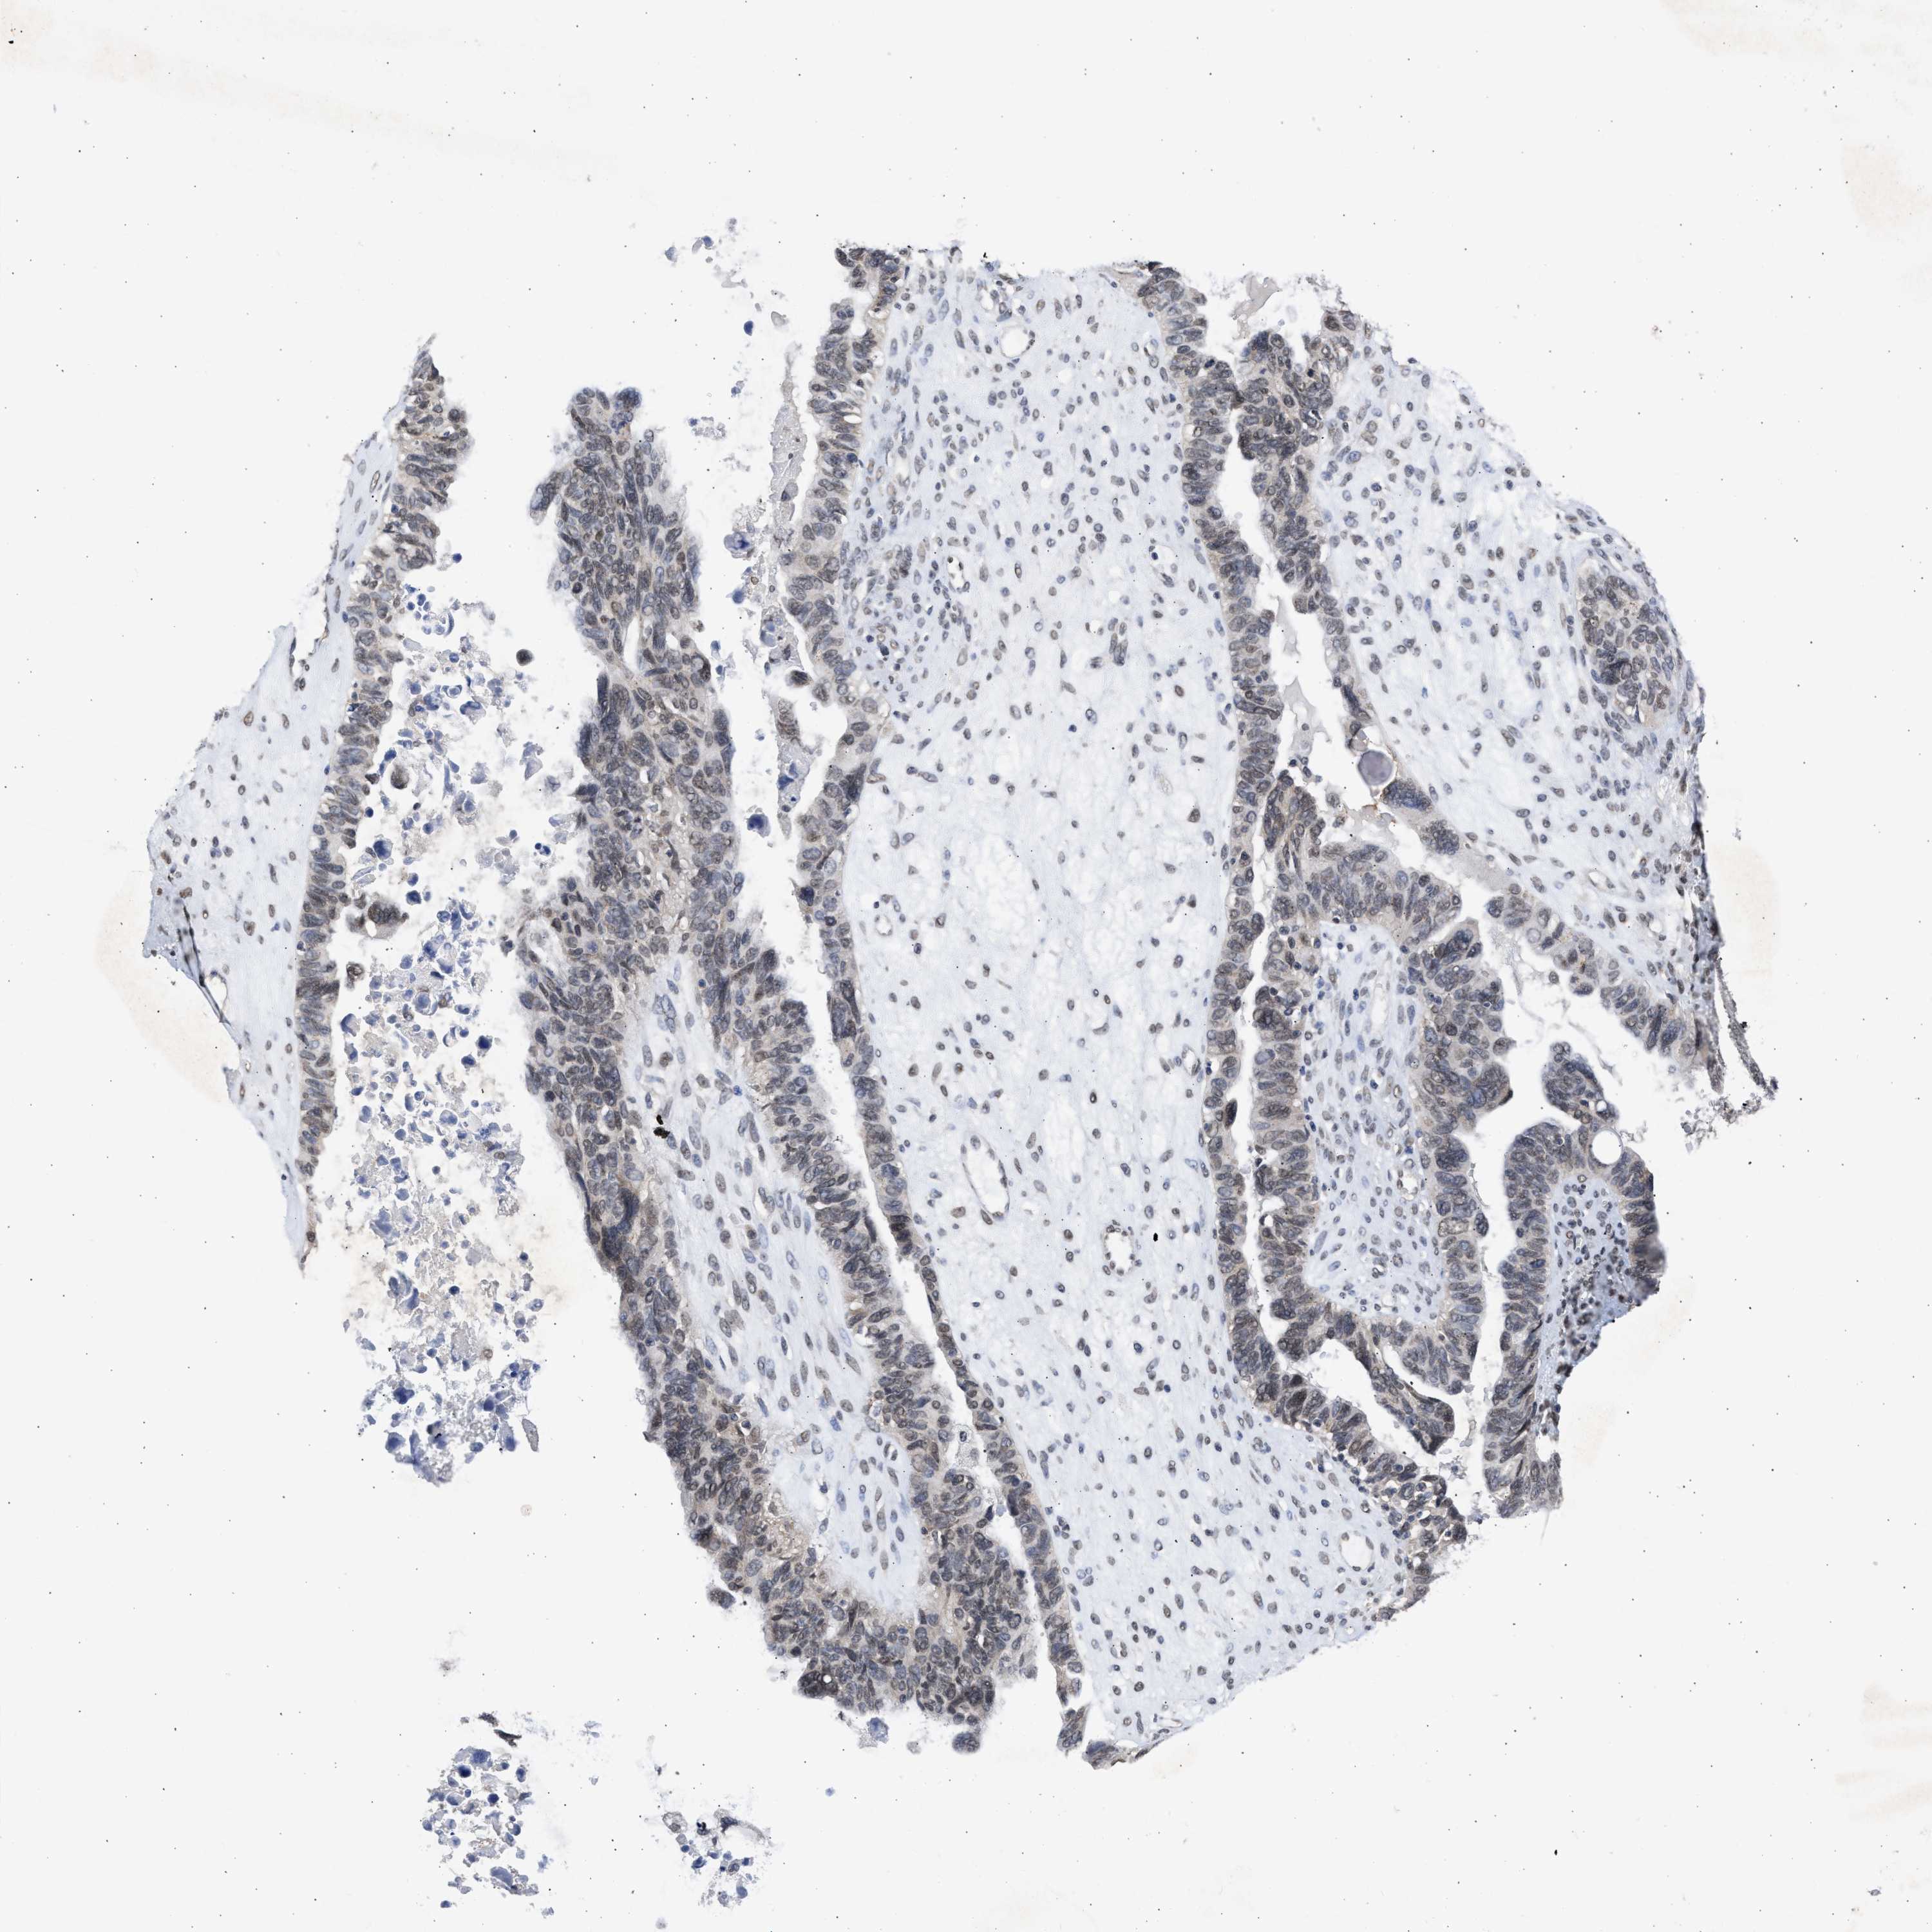

OVARIAN CANCER - Protein expressioni

A mouse-over function shows sample information and annotation data. Click on an image to view it in a full screen mode. Samples can be filtered based on level of antibody staining by selecting one or several of the following categories: high, medium, low and not detected. The assay and annotation is described here.

Note that samples used for immunohistochemistry by the Human Protein Atlas do not correspond to samples in the TCGA dataset.

Antibody stainingi

Antibody staining in the annotated cell types in the current human tissue is reported as not detected, low, medium, or high, based on conventional immunohistochemistry profiling in selected tissues. This score is based on the combination of the staining intensity and fraction of stained cells.

Each image is clickable and will lead to virtual microscopy that enables deeper exploration of all samples and also displays staining intensity scores, fraction scores and subcellular localization as well as patient and tissue information for each sample.

Antibody HPA018401

Cystadenocarcinoma, serous, NOS